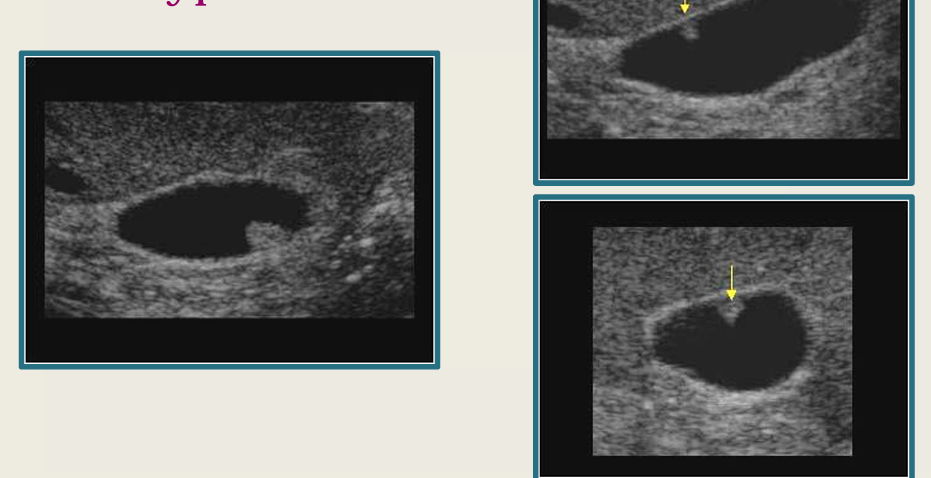

term image

cholelithiasis

2

New cards

WES sign

3

sludge

4

porcelain GB